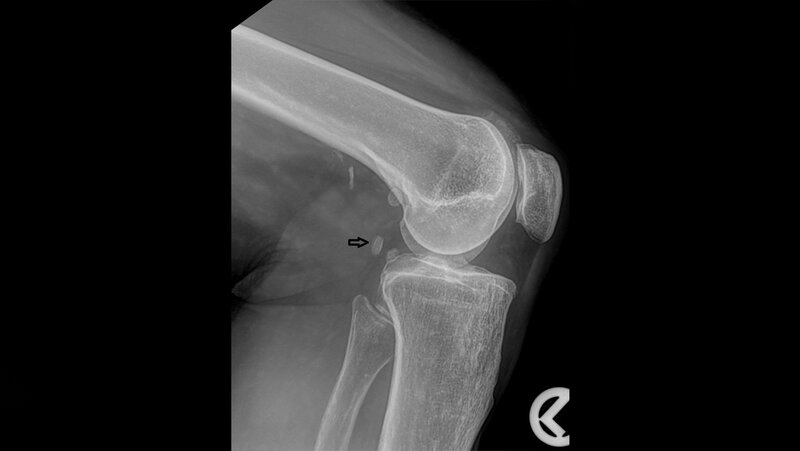

Die Fabella ist ein Sesambein im lateralen Kopf des M. gastrocnemius. Es kommt bei etwa 10 bis 30 % der Bevölkerung vor und kann das Fabella-Schmerz-Syndrom oder auch eine Lähmung des N. fibularis communis auslösen.

The Fabella is a sesamoid bone that is embedded in the lateral head of the gastrocnemius muscle. It is present in approximately 10 to 30 % of the general population. It can lead to various pathologies such as fabella pain syndrome and common fibular nerve palsy.